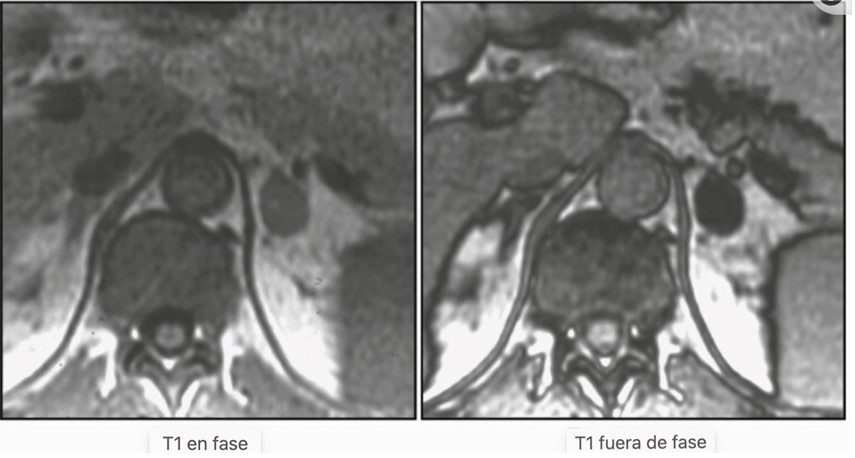

La resonancia magnética es una modalidad de imagen basada en radiación no ionizante que utiliza señales débiles de onda de radio emitidas por los tejidos del cuerpo cuando el cuerpo se coloca en un campo magnético fuerte y se aplican pulsos de radiofrecuencia. Las ventajas de la resonancia magnética sobre la TC son su falta de exposición a la radiación, la falta de medios de contraste a base de yodo y su resolución de contraste tisular superior. Los tiempos de escaneo más largos, la claustrofobia y los dispositivos incompatibles con la resonancia magnética in situ son las principales desventajas de esta. Para la diferenciación de las masas suprarrenales benignas y malignas, la técnica de resonancia magnética de la imagen de desplazamiento químico se utiliza más comúnmente. La imagen de desplazamiento químico se basa en el hecho de que, dentro de los campos magnéticos, los protones en el agua vibran a una frecuencia ligeramente diferente a la de los protones en los lípidos. Como resultado, el agua y los protones de grasa oscilan dentro y fuera de fase entre sí.

Los adenomas suprarrenales con un alto contenido de lípido intracelular generalmente pierden intensidad de la señal en las imágenes fuera de fase en comparación con las imágenes en fase, mientras que las lesiones malignas y los feocromocitomas (pero también algunos adenomas suprarrenales pobres en lípidos) que carecen de lípido intracelular permanecen sin cambios y conservan su señal.(22)

Las unidades de intensidad de la señal de RM son unidades arbitrarias, a diferencia de la TC, y por lo tanto están sujetas a numerosas variaciones técnicas. La evaluación visual simple de la pérdida de intensidad de la señal es diagnóstica en la mayoría de los casos, reservando los métodos cuantitativos a casos menos claros. Las directrices más recientes sugieren que la evaluación de la resonancia magnética de las lesiones suprarrenales debe usarse principalmente como una herramienta de resolución de problemas.

Hay métodos cualitativos (análisis visual) y cuantitativos de evaluación de imágenes que implican la evaluación del cambio en la intensidad de la señal de las lesiones suprarrenales entre secuencias en fase y fuera de fase.(24)

Una revisión sistemática reciente y un metaanálisis informaron que el análisis visual y el análisis cuantitativo del índice de intensidad de la señal suprarrenal y la relación suprarrenal-bajo tienen una alta precisión para la detección de adenoma rico en lípidos (95%-98%), y el rendimiento diagnóstico no mejora significativamente por el índice de intensidad de la señal suprarrenal o la relación suprarrenal a bajo(24) (Figura 2). En consecuencia, si se detectan IA en la resonancia magnética y los hallazgos son inequívocos para un adenoma benigno rico en lípidos, es posible que no se justifiquen más imágenes.